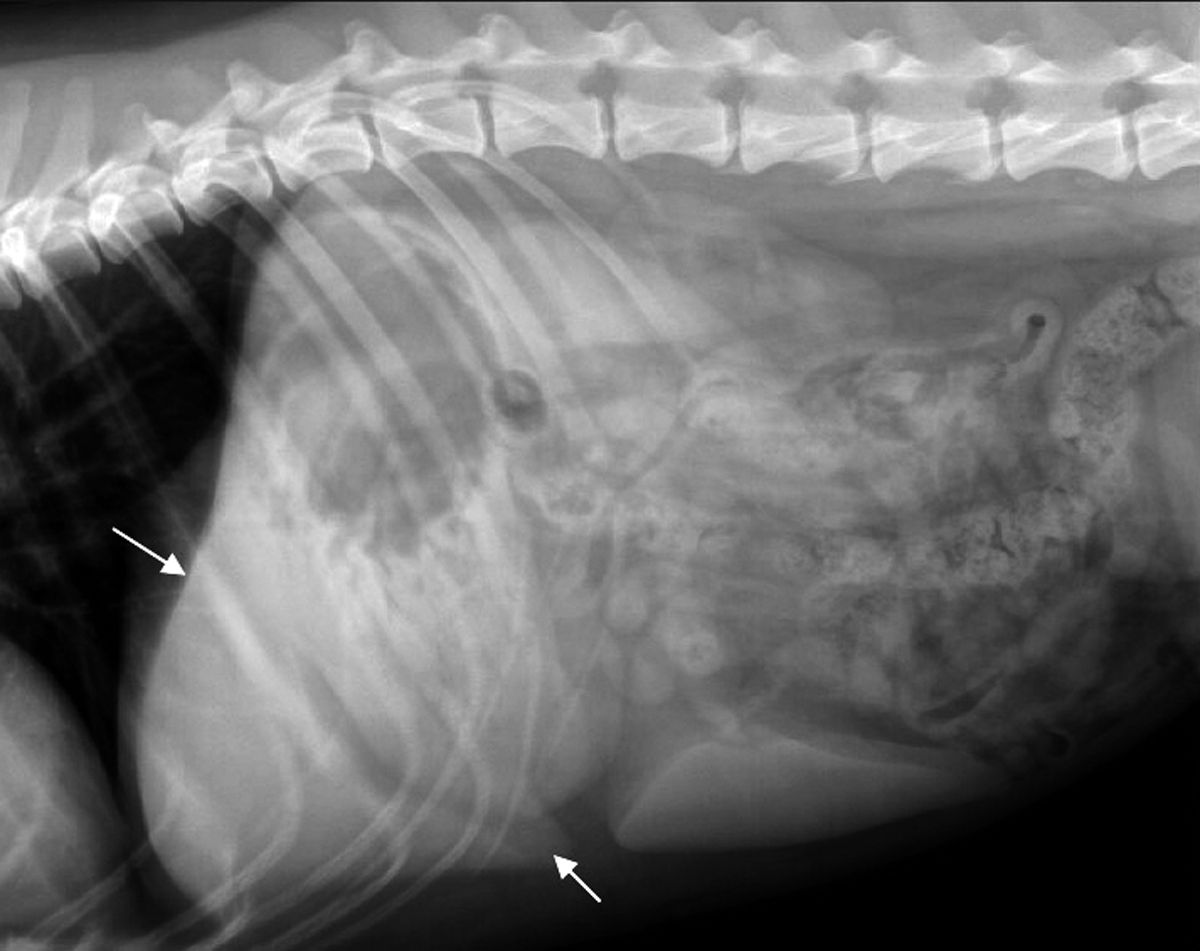

Liver Mass Dog X Ray. However, the microscopic spread of the tumor to other organs cannot be detected with these tests. although liver tumors cannot normally be diagnosed by clinical signs,. Ultrasound can determine if the tumor is massive, nodular, or diffuse, and whether it is in more. ultrasound is the most common diagnostic that is used to identify liver tumors. the most common primary liver tumor in dogs (second most common primary liver tumor in cats) is hepatocellular carcinoma (hcc). here’s what to know about the signs of liver cancer in dogs, diagnosis, and possible treatments, and the impact liver cancer may have on your dog’s lifespan. ultrasound is more sensitive for the detection of masses on the liver. dogs often have clinical signs that could be attributed to a liver mass.6 in some dogs, however, hepatic masses are found incidentally.16 historical findings can include anorexia, hyporexia, lethargy, weakness, vomiting, weight loss, diarrhea, polyuria, and polydipsia.1,6 clinical signs can include hepatomegaly, palpable abdominal mass.

ultrasound is the most common diagnostic that is used to identify liver tumors. However, the microscopic spread of the tumor to other organs cannot be detected with these tests. Ultrasound can determine if the tumor is massive, nodular, or diffuse, and whether it is in more. dogs often have clinical signs that could be attributed to a liver mass.6 in some dogs, however, hepatic masses are found incidentally.16 historical findings can include anorexia, hyporexia, lethargy, weakness, vomiting, weight loss, diarrhea, polyuria, and polydipsia.1,6 clinical signs can include hepatomegaly, palpable abdominal mass. although liver tumors cannot normally be diagnosed by clinical signs,. the most common primary liver tumor in dogs (second most common primary liver tumor in cats) is hepatocellular carcinoma (hcc). ultrasound is more sensitive for the detection of masses on the liver. here’s what to know about the signs of liver cancer in dogs, diagnosis, and possible treatments, and the impact liver cancer may have on your dog’s lifespan.